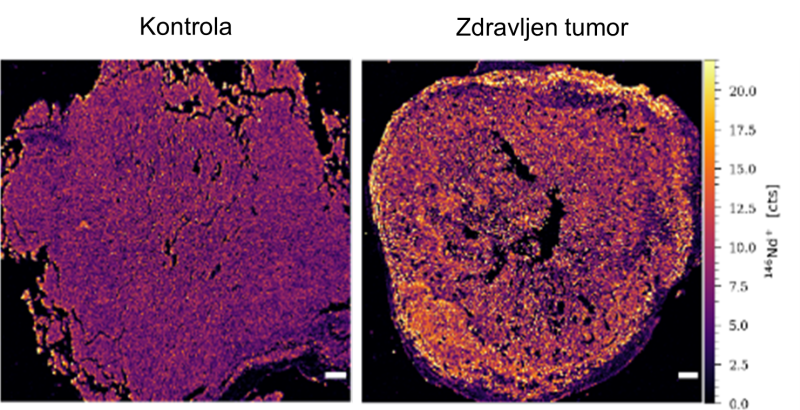

Slika 3: Prerez kontrolnega tumorja melanoma (levo) in s citokini obogateno piroptozo zdravljenega tumorja melanoma (desno), kjer lahko vidimo infiltracijo imunskih celic (rumena barva) v tumor.

Delovanje s citokini obogatene piroptoze smo preizkusili na tumorjih z različnimi imunološkimi potnimi listi, ki smo jim s pomočjo elektroporacije vnesli plazmidno DNK, ki nosi zapis za posamezne terapevtske proteine. Pokazali smo, da aktivacija por gasdermina D v tumorju povzroči piroptotično smrt rakavih celic, terapija pa je bila najbolj učinkovita na modelu mišjega raka debelega črevesa in danke CT26, ki spada pod imunološko vroče tumorje. Pri njem je prišlo do zavrtja rasti tumorjev in dolgotrajne preživelosti pri 80 % zdravljenih miši. To je bilo seveda mogoče pričakovati, saj so v tumorjih z vročim fenotipom prisotne celice imunskega sistema, vendar pa tumorsko mikrookolje zavira njihovo delovanje. Z aktivacijo celične smrti smo tako uspešno preoblikovali imunosupresivno tumorsko mikrookolje in spodbudili delovanje imunskih celic. Terapija je bila uspešna tudi v primeru imunološko hladnih tumorjev, kjer je s citokini obogatena piroptoza na modelu kožnega melanoma B16F10, ki velja za agresivno obliko raka, povzročila regresijo tumorjev in dolgotrajno preživetje 40 % miši. Tako smo pokazali, da s citokini obogatena piroptoza deluje na tumorje ne glede na njihov izvor in imunološki potni list. Poleg tega smo z eksperimenti potrdili, da je za uspešno delovanje s citokini obogatene piroptoze nujna podpora celic imunskega sistema, s čimer smo dokazali, da prav zares govorimo o imunoterapiji raka. Hkrati pa smo pokazali tudi, da s citokini obogatena piroptoza izzove sistemsko protitumorsko imunost, ki jo posredujejo predvsem citotoksične celice CD8+ T in naravne celice ubijalke.